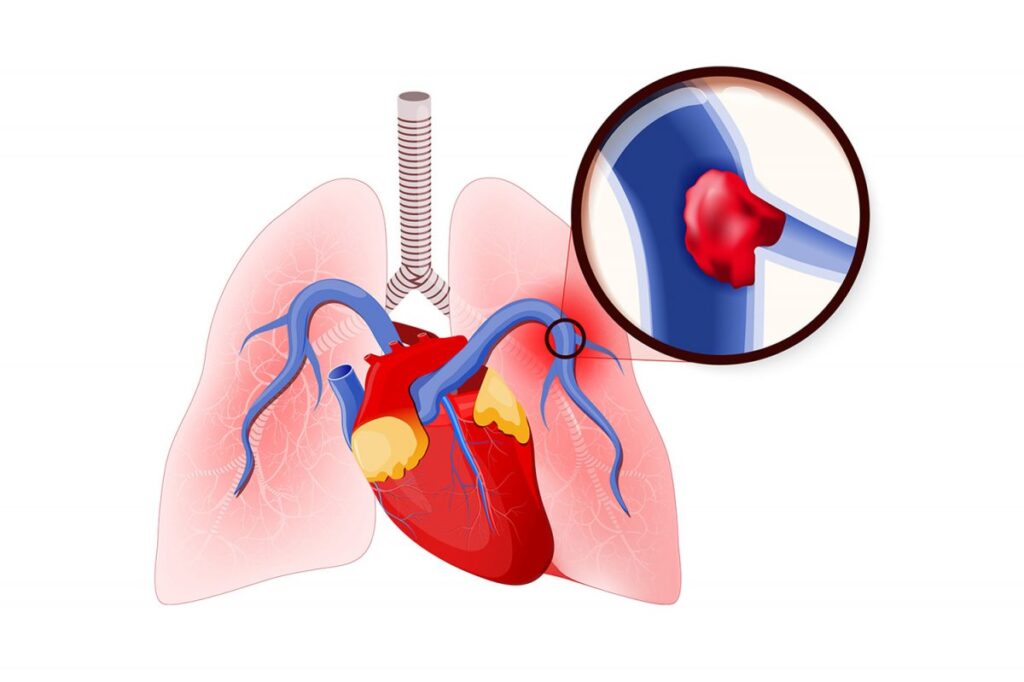

حمید عمادی، متخصص بیماریهای عفونی و گرمسیری با بیان اینکه آمبولی ریه به اثر لخته شدن خون در ریه و آسیب به عملکرد این اندام گفته میشود، اظهار کرد: ویروس کرونا تاثیر شدیدی بر بدن و ریه می گذارد و در نهایت کاهش اکسیژن باعث اختلال در عملکرد و التهاب ریه خواهد شد، در واقع ویروس کرونا بر فرآیند ایجاد آمبولی موثر است.

عمادی با بیان اینکه عروق یا رگها هم تحت تاثیر التهاب ریوی قرار میگیرند، تاکید کرد: از آن جایی که در فرد مبتلا به کرونا التهاب شدید ریوی یا عروقی ایجاد میشود و تمامی رگها ملتهب میشوند در نهایت احتمال بروز لخته در عروق زیاد میشود و این لختهها با گیر کردن در مغز و قلب بروز سکته مغزی و سکته قلبی را بسیار محتمل میکنند، همچنین میتوانند در رگهای موجود در ریه گیر کرده و آمبولی ریه ایجاد کنند.

متخصص بیماریهای عفونی و گرمسیری ادامه داد: به طور معمول بیماران کرونایی که دچار التهاب شدید ریوی شده اند و در بیمارستان بستری هستند با مصرف داروهای ضد انعقاد به منظور جلوگیری از لخته شدن خون شان تا حدودی درمان خواهند شد تا به اینصورت از ابتلای آنها به آمبولی ریه پیشگیری کنیم.

او گفت: آمبولی ریه و سکته قلبی و سکته مغزی میتواند منجر به مرگ افراد شود، اما با مصرف داروهای ضد انعقاد درمان میشوند البته در برخی موارد هم بیمار جان خود را از دست میدهد.

عمادی در پایان یادآوری کرد: با تشخیص زودهنگام افراد مبتلا به آمبولی ریه و مصرف متناسب دارو شانس بهبودی آنها افزایش پیدا میکند در غیر اینصورت احتمال مرگشان وجود دارد.